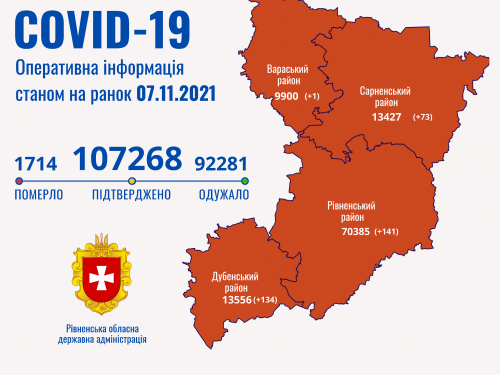

Пів тисячі - у важкому стані, 9 жителів Рівненщини померли за добу від коронавірусу